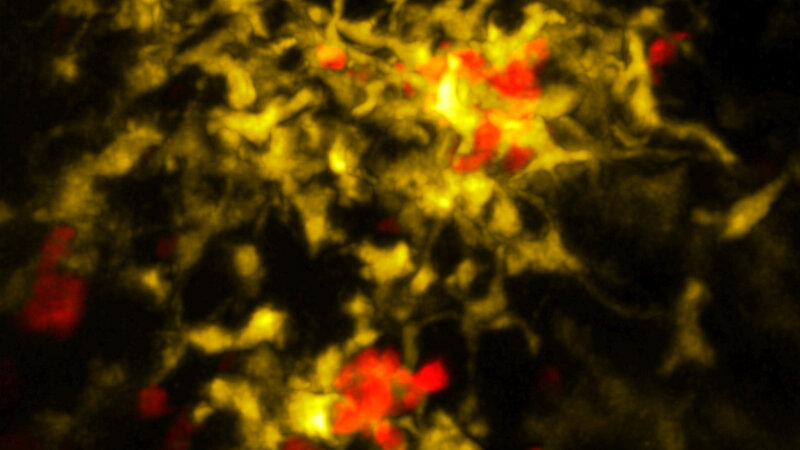

Direkt nach dem Kontakt mit dem Fremdstoff stößt die Killerzelle daher eine Art chemischen Hilferuf aus. Aufnahmen eines Spezial-Mikroskops zeigen erstmals, wie sich daraufhin bestimmte Spezialzellen der Körperabwehr zu ihr aufmachen. Nach ihrer Ankunft setzen diese Helfer verschiedene Immunprozesse in Gang. Erst dadurch wird die Killerzelle vollständig aktiviert.